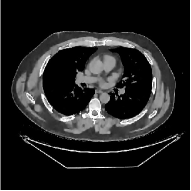

This section compares the reconstruction quality and runtime among the proposed MBIR method, PWLS-ST-, and other three MBIR methods, PWLS-EP, PWLS-DL, and PWLS-ST-. Table I shows that, for both 2D and 3D sparse-view CT reconstructions of the XCAT phantom, the proposed PWLS-ST- model outperforms PWLS-EP and PWLS-ST- in terms of RMSE. In addition, PWLS-ST- using a square transform (of size ) achieves lower RMSE than PWLS-DL using an overcomplete dictionary (of size ) for 2D sparse-view reconstructions. Fig. 3(a) and Fig. 4 show the reconstructed images for 2D and 3D phantom experiments, with different reconstruction models and different number of views. (See the corresponding error maps in the supplement.) The proposed PWLS-ST- consistently gives more accurate image reconstructions compared to other MBIR methods. Specifically, PWLS-ST- has smaller errors in the heart region (see zoom-ins in Fig. 3(a)) of 2D reconstructions than PWLS-DL and PWLS-ST-. In addition, compared to PWLS-ST-, PWLS-DL and PWLS-ST- have some ringing artifacts around the edges with high transition, e.g., edges between air and soft tissues. (See a comparison of profiles of PWLS-ST- and PWLS-ST- in the supplement.) In particular, PWLS-ST- and PWLS-DL give more visible ringing artifacts for 2D reconstruction from fewer views, and PWLS-ST- has these ringing artifacts for 3D reconstructions regardless of the number of views (see zoom-ins in Fig. 4). Table II reports runtimes of different MBIR methods in reconstructing the -views XCAT phantom scan. (FBPConvNet is a non-MBIR method and its runtime for processing a image is approximately one second with a TITAN Xp GPU.) While providing better reconstruction quality, the proposed Algorithm 1 of PWLS-ST- has shorter runtime compared to the algorithms of PWLS-DL and PWLS-ST- in Section III-A. Similar to the PWLS-EP algorithm, the reconstruction time of the PWLS-DL, PWLS-ST-, and PWLS-ST- algorithms can be further reduced by using ordered subsets [51].

Fig. 3(b) shows that when tested on the clinical scan data, the proposed PWLS-ST- method improves reconstruction quality in terms of noise and artifacts removal (e.g., see zoom-ins for soft-issue regions), and edge preservation (e.g., see zoom-ins for bone regions), compared to PWLS-EP and PWLS-ST-. Compared to PWLS-DL, PWLS-ST- achieves comparable image quality, but requires less computational complexity.

The benefit of the proposed PWLS-ST- over PWLS-ST- can be explained when there exist some outliers for some : in (12) gives equal emphasis to all sparse codes – from small to large coefficients that generally correspond to edges in low- and high-contrast regions, respectively – in estimating ; however, PWLS-ST- adjusts to mainly minimize the outliers, i.e., it may not pay enough attention to reconstruct regions with small coefficients. The histogram results in Fig. 1 reveal model mismatch of PWLS-ST- over the iterations. Fig. 3, Fig. 4, and Table I show that PWLS-ST- can moderate model mismatch, and provides more accurate reconstruction than PWLS-ST-.

![]() |

| (a) 2D fan-beam CT experiments |

| (b) 3D axial cone-beam CT experiments |